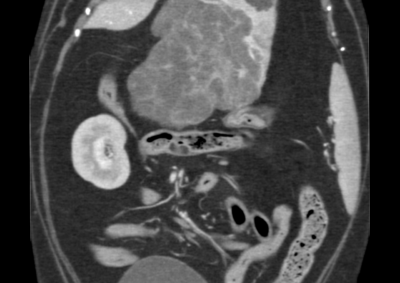

注意 ボタンをクリックした先に、治療中および手術中の画像が説明で使用されている場合がございます。 そのような画像に弱い方は閲覧なさらないようお願いいたします。 整形外科 若齢犬の橈骨固定術 #271 整形外科 前十字靭帯断裂(中型犬)に対するCBLO #255 整形外科 超小型犬に対する上腕骨遠位Y字骨折 整形外科 大型犬の前十字靭帯疾患(慢性経過)に対するCBLO #254 整形外科 橈骨固定術 #270 整形外科 膝蓋骨内方脱臼に対する人工滑車置換術 PGR #23 整形外科 犬の前十字靭帯(疾患)部分断裂に対するCBLO #253 整形外科 犬の前十字靭帯断裂に対するCBLO #252 整形外科 膝蓋骨内方脱臼+前十字靭帯断裂に対するPGR#22・LSS 整形外科 大腿骨骨折 整形外科 橈骨固定術 #269 整形外科 上腕骨外顆骨折の癒合不全 123456> 症例カテゴリー 放射線治療整形外科軟部組織外科脳神経外科内科腫瘍外科救急・集中治療リハビリテーション科腫瘍内科内視鏡科脳神経科呼吸器外科中医・漢方猫の腎移植循環器科